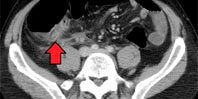

Исследование почти 1,7 миллиона человек показало: удаление аппендикса снижало риск болезни Паркинсона на 19,3%. Альфа-синуклеин убивает нейроны. В норме он присутствует в аппендиксе всех людей. Что заставляет его перемещаться в мозг, вызывая проблемы, ученые не знают.